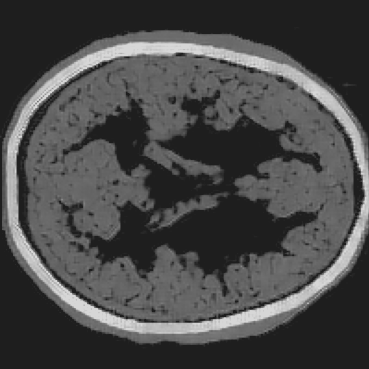

Refer to caption

(a) Partial-transducer dataset

Figure 8: Stacked TRA Image with (a) Partial-transducer dataset and (b) Full-transducer dataset

To evaluate performance, we construct two acquisition setups from the same horizontal 2D slice of the phantom: (i) an idealized full-transducer dataset (Figure 4(b)) providing near-uniform coverage along the head contour, and (ii) a partial-transducer dataset (Figure 7) designed to reflect practical acquisition constraints. In the partial setup, a linear array with 51-element is repositioned around the head; for each view, the central element transmits and all other 50 elements receive. The partial setup includes 50 sweeps covering the full 360, meaning that for each sweep, the source and receivers rotate by 360/50=7.2360/50=7.2^{\circ}. Sweeping 50 views yields, per 2D slice, a channel tensor of shape (T,Ns,Nr)=(5001,50,50)(T,N_{s},N_{r})=(5001,50,50). The key distinction between these two datasets is their aperture: full-transducer provides near 360 coverage in a single placement, whereas partial-transducer attains coverage by aggregating neastest 50 receivers in a single placement, which is only around 36. Particularly, the partial-transducer setup includes only 50 sweeps, while the full-transducer setup uses all receivers covering the entire brain, with each transducer acting as a source in turn while the others serve as receivers. Compared to the full-transducer, the partial-transducer achieves coverage by combining a much smaller number of views. For each sweep, we generate the forward wavefield g(𝐱,t|𝐠){{g}}(\mathbf{x},t|\mathbf{g}) and the back-propagated wavefield p~(𝐱,t|𝐠)\tilde{{p}}(\mathbf{x},t|\mathbf{g}) and generate the TRA fragment with Eq. (7) (example in Figure 7). With the physical TRA method, the TRA fragment can be stacked to give the stacked TRA image. To validate the differences between the two datasets, we generated stacked TRA images using both datasets, as shown in Figure 8. As shown in Figure 8(b), the full-transducer dataset provides significantly greater detail in internal structures. Despite higher levels of noise and artifacts caused by the limited number of views, the partial-transducer dataset is still capable of capturing some meaningful tissue structures.